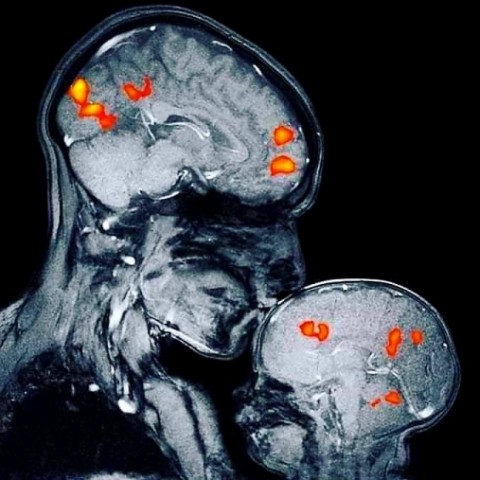

Esta preciosa imagen es la primera resonancia tomada de una madre, la neurocientífica Rebecca Saxe, besando a su hijo de 2 meses. Se pueden apreciar las zonas cerebrales que se iluminan con un beso, es la primera imagen que muestra el vínculo madre hijo.

"Besar causa una reacción química en nuestro cerebro, incluyendo una explosión de la hormona oxitocina, "la hormona del amor" que nos ayuda a establecer vínculos de apego... Asimismo besar activa nuestro sistema de recompensa, liberando dopamina, la cual nos hace sentir bien; vasopresina que une a las madres con los bebés y las parejas románticas entre sí; y la serotonina que ayuda a regular nuestro estado de ánimo"... dato muy interesante.